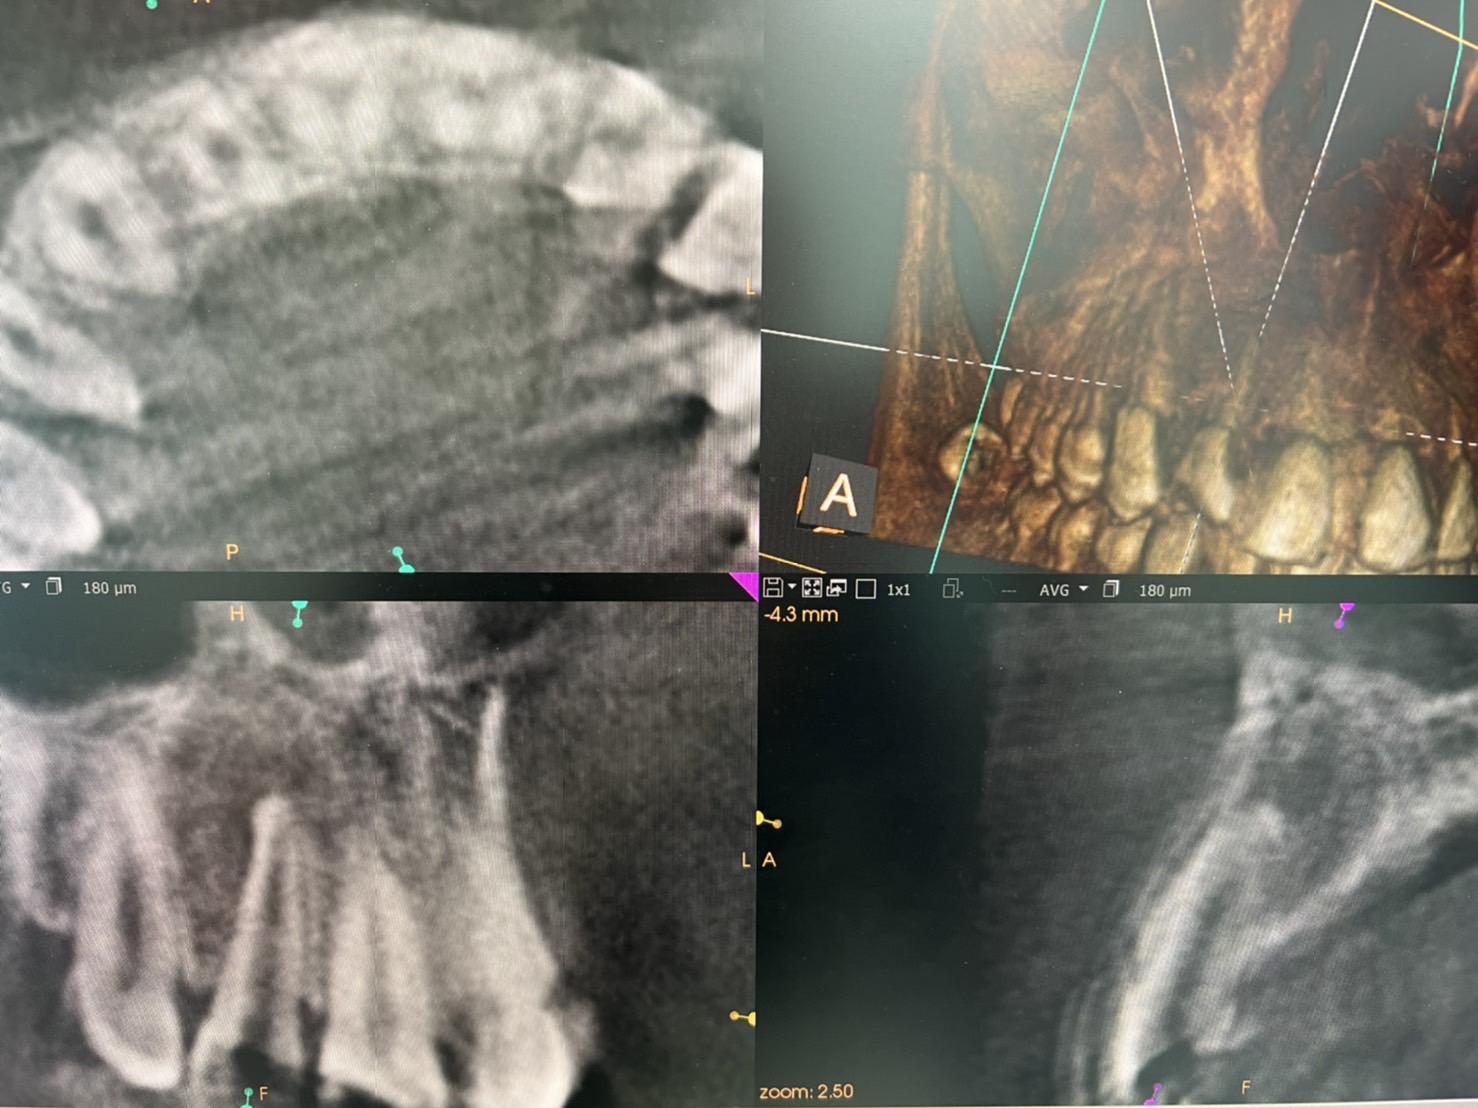

新大久保歯科医院 副院長 猪子佳恵です。 今回は久しぶりに根管治療の症例をアップしようと思います! 昨年12月中旬に根管治療を開始した患者様 病変も大きく、歯もグラグラしておりCT撮影をしたところ根の先に直径1㎝程の膿の袋が出来ておりました。

これは虫歯だけが原因で起きたのではなく、虫歯に噛み合せが助長して起きた結果です。 しっかり原因を突き詰め、除去する事でたった3か月でここまで回復

無事に次回には被せ物が入るところまできました

病変が大きく、歯もグラグラになってるからと直ぐに諦める必要はありません。 場合によってはきちんと治療し、まだまだ歯を使う事が出来るのです!